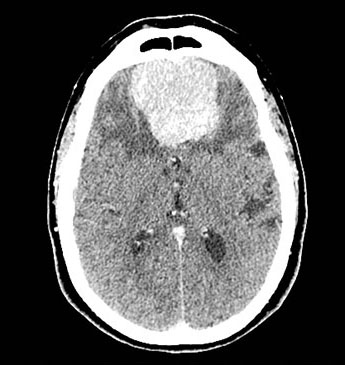

脑膜瘤绝大多数都是良性的,生长缓慢,切除之后不容易复发。但是有一些脑膜瘤却是恶性的,它们可以侵蚀颅骨,把头骨都“吃掉”,还有一些不容易切干净,存在复发的可能。

世界卫生组织(WHO)根据脑膜瘤的良恶性程度,将脑膜瘤分为了三级,I/II/III三级,级别越高,恶性程度越高,越容易侵犯周边的组织,也越容易复发。

这是一个III级的脑膜瘤,这是利用计算机模拟形成的图像,我们可以看到肿瘤已经破坏了患者的头骨。

但是,大家也不要担心,大多数脑膜瘤都是良性的,生长非常缓慢,切除之后不再复发。